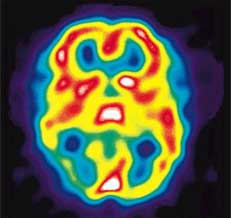

Brain with Migraine HeadacheAlthough the exact cause of migraine is still unknown, there is evidence to suggest that migraine headaches may be triggered by trauma to the head and neck area. The pain may not develop until years later. The standard approach to managing migraines has been drug therapy; drugs, however, do not treat the root cause of the disorder and often have unpleasant side effects.

NUCCA can help provide migraine pain relief by alleviating any misalignments in the vertebrae of the upper cervical spine (upper neck) caused by trauma such as auto accidents or sports injuries, as well as poor posture. These misalignments cause irritation to the nerves traveling between the brain and spinal cord and to the blood vessels traveling to the head. Nerve irritation and altered blood flow has been directly associated with migraines. By correcting the vertebrae in the upper neck, normal nerve and blood flow is returned and many patients suffering from migraine headache pain are able to get long term relief from their symptoms.